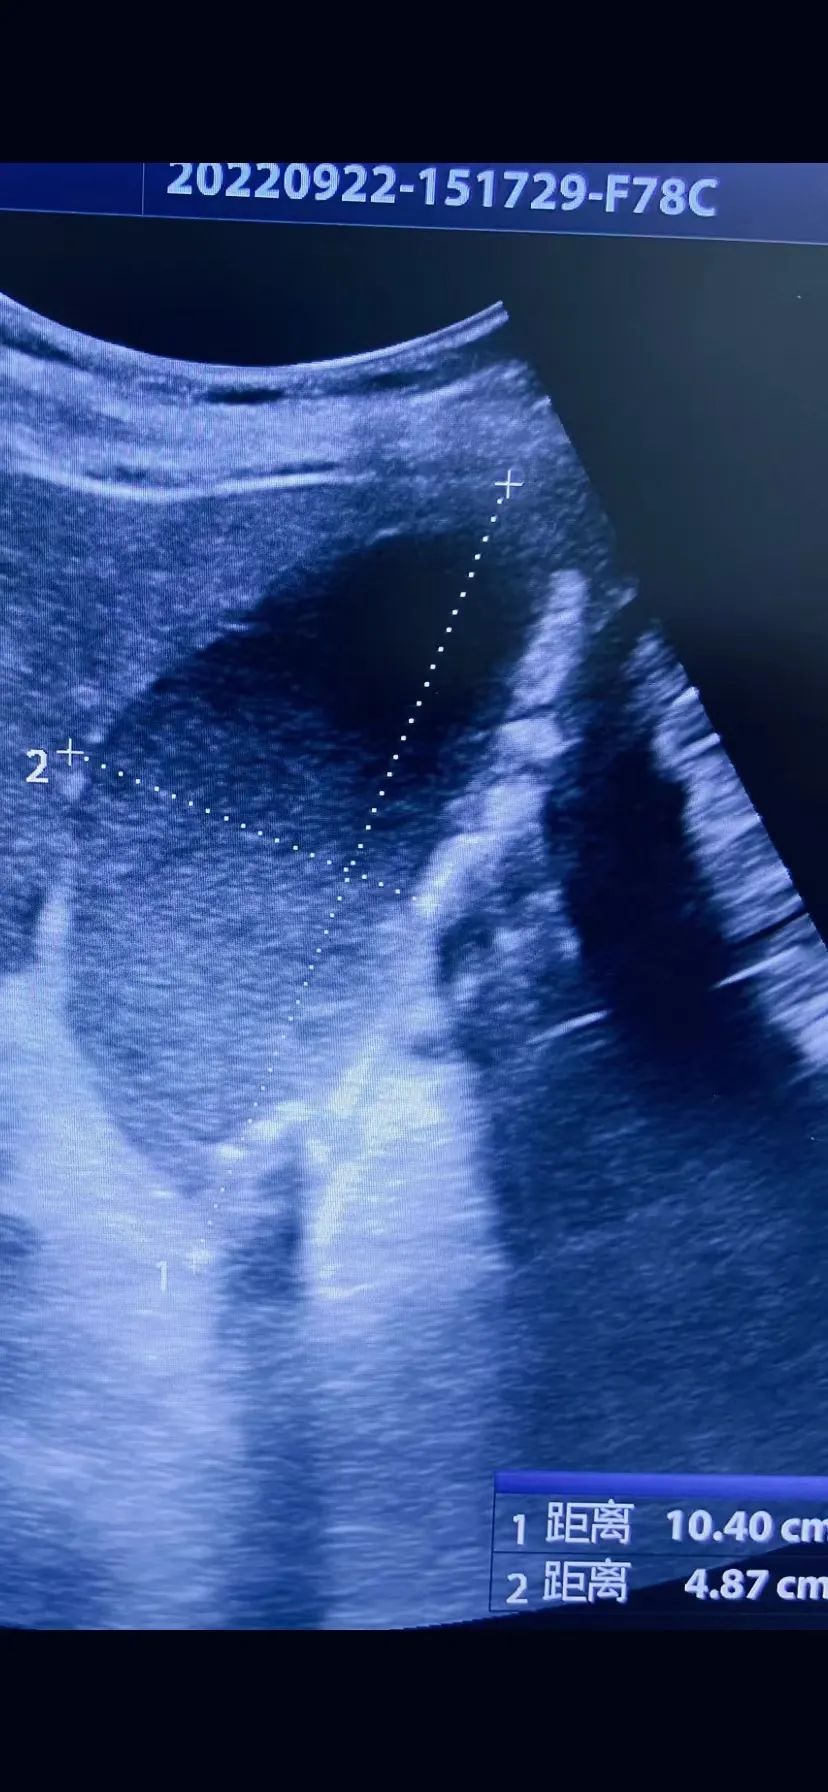

今年59岁的杨女士,不久前因结肠癌行过手术及化疗,本次腹痛伴呕吐2天入住医院肿瘤血液内科,住院期间行彩超显示“急性胆囊炎、胆囊多发结石、胆囊肿大”,患者当时胆囊体积显著增大约104x48mm,张力大,医师考虑杨女士腹痛、呕吐为胆囊疾病所致。因患者年龄偏大,基础疾病多且合并其它并发症,经医院肝胆疝外科魏仁军主治医师会诊后认为患者手术风险大,目前暂时无法耐受手术切除,但是根据病情急需胆囊减压,与肿瘤科李宏新医师和超声科刘彦主任商量后,决定行超声引导下经皮经肝胆囊造瘘(PTGD)术。

术前胆囊大小104X48.7mm,形态饱满张力大(左),

术后胆囊大小51X20mm,体积明显缩小(右)